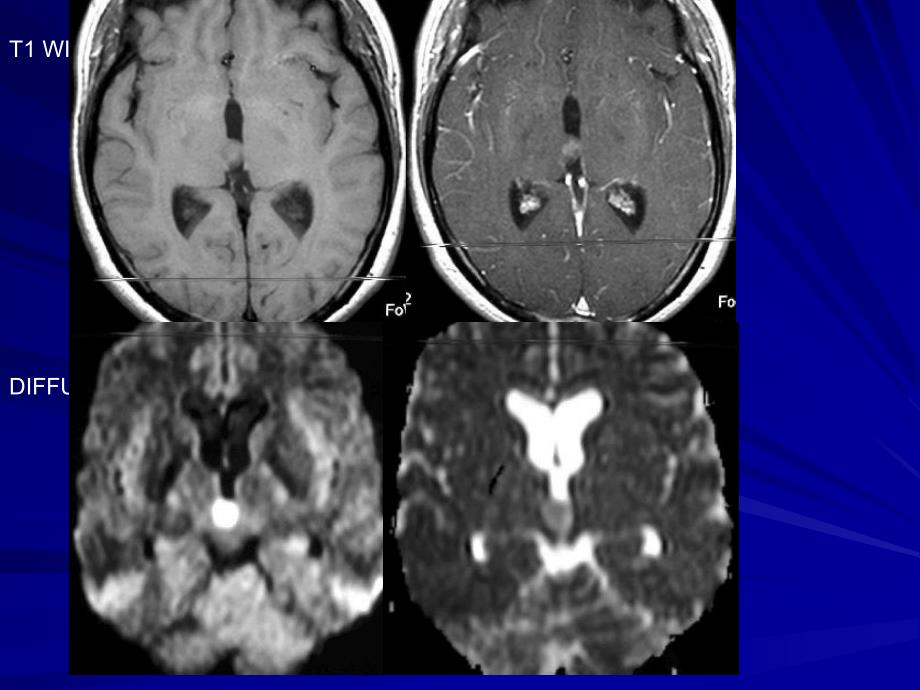

1、脑室肿瘤占中枢脑室肿瘤占中枢NSNS肿瘤的肿瘤的1010左右左右;根据起源可分两类根据起源可分两类:第一类 起源于脑室系统肿瘤;第二类 起源于脑实质而长入脑室 系统的肿瘤;脑室肿瘤概论脑室肿瘤概论T1 WIPOST-CONTRASTDIFFUSIONADC MAPFLAIRPOST-CONTRAST有一定的发病年龄和好发部位;影像学表现复杂多样无特征性;瘤周水肿不明显,脑积水常见。脑室肿瘤概论脑室肿瘤概论成人脑室肿瘤(1)部 位常 见 肿 瘤侧脑室区前角 体部三角区后角及下角区高度恶性AG、SGA、中枢神经细胞瘤、室管膜下瘤星形细胞瘤、室管膜瘤、中枢神经细胞瘤、室管膜下瘤、转移瘤、淋巴瘤脑膜瘤

4、内 (15)室管膜瘤室管膜瘤病理上分四型:上皮型、乳头型、粘液型和细胞型,后者常见。室管膜瘤的影像学室管膜瘤的影像学平扫:CT 等/低密度;MRT1WI等或低信号;T2WI不均匀高信号。肿瘤内可见囊变、钙化、出血。增强扫描:多呈轻度到中度强化常可见不均匀强化。第四脑室内室管膜瘤。右侧脑室内室管膜瘤。右半球内脑室外室管膜瘤右额脑室外室管膜瘤。室管膜下瘤(室管膜下瘤(SubependymomaSubependymoma)较为罕见的良性肿瘤4060岁好发,大多无症状,晚期致梗阻性脑积水。部位:好发于双侧脑室前角和体部,延髓下部者可突入四脑室。室管膜下瘤病理学室管膜下瘤病理学为边界清楚的分叶状肿块镜下